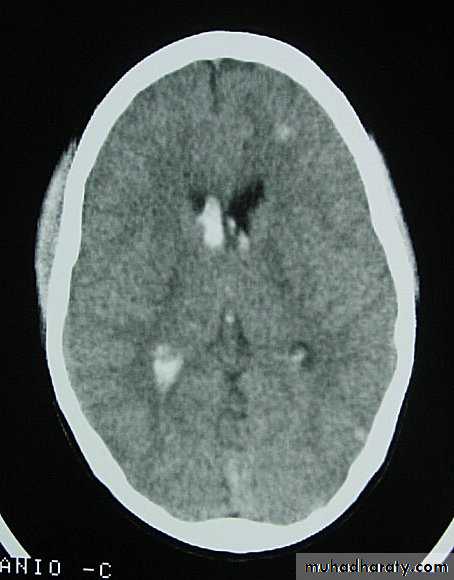

1. Diffuse Axonal Injury

Prolonged post-traumatic state in which there is loss of consciousness from the time of injury that continues beyond 6 hours.Occurs as a result of mechanical shearing at the grey-white matter interface.

This causes disruption and tearing of axons, myelin sheaths and blood capillaries.

Severity can range from mild damage with confusion to coma and even death.